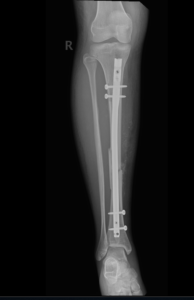

if the fracture is displaced, surgery may be needed to put the bone back into the correct position and fix the bone with Plates & screws or nails for adequate healing to occur.

- Tibia Fractures.